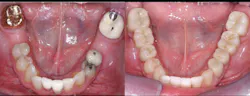

• Use resin-modified glass ionomer (RMGI) cement for zirconia restorations when the tooth preparations have near-optimum characteristics. See Figures 4 through 6 for examples of these characteristics. Most clinicians and researchers would agree that the tooth preparation should be at least 4 mm in height from the gingival margin to the occlusal table, and that the lack of parallelism of the preparation walls should be up to, but not more than, 20 degrees from the long axis of the tooth being prepared.

Figures 4-6: Images showing an adequate impression, the die of an adequate tooth preparation, and the resultant full-zirconia crowns.

Figure 6